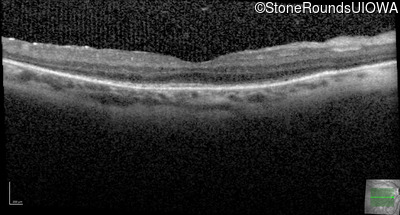

Optical Coherence Tomography - Right - 20/50 +1

Exemplar / OCT Stack